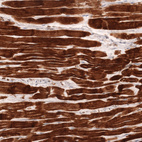

Immunohistochemistry analysis in human heart muscle and skeletal muscle tissues using AMAb91857 antibody. Corresponding TNNT2 RNA-seq data are presented for the same tissues.